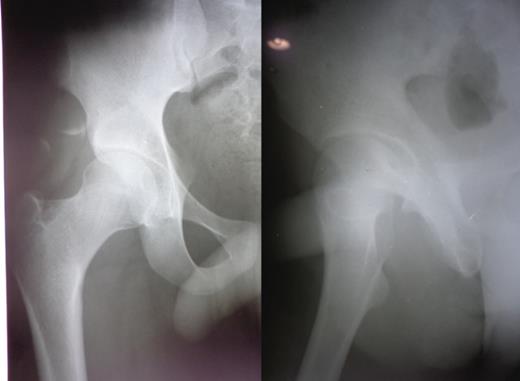

A 23-year-old male pavement dweller was brought to the emergency department of this hospital after being hit by a tempo. The patient was in a state of shock with an open right-sided anterior hip dislocation with the femoral head being visible in the inguinal region (Fig. 1). The neurovascular status of the right lower limb was intact. Immediate resuscitation was done and hip radiographs (Fig. 1) were taken, which showed an anterior-inferior dislocation with an inferior pubic ramus fracture on the left side. The patient was immediately transferred to the operating room where the wound was thoroughly debrided and the femoral head was relocated within 5 hours of sustaining the trauma (Fig. 2). The wound after surgical debridement was 8 × 6 cm in dimensions, which was primarily closed after checking for the stability of the reduction. The patient was started on intravenous metronidazole, amikacin and ceftriaxone for 5 days, followed by oral amoxicillin for a week. The patient was kept non-weight-bearing on skin traction for 6 weeks. The wound healed satisfactorily with no evidence of infection, nor any episode of re-dislocation at 6 months (Fig. 3). The patient was unfortunately lost to follow-up.

Figure and radiograph showing an open anterior hip dislocation.